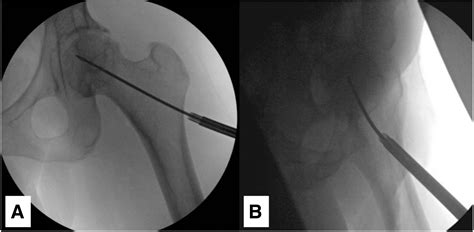

The management of Avn disease hip is highly individualized. If caught in the very early stages (Stage I or II), doctors may attempt "joint-sparing" procedures. These are designed to preserve your natural bone and delay the need for a full replacement.

Surgical interventions often include:

• Core Decompression: A surgeon removes a portion of the inner bone to reduce pressure and encourage new blood vessel growth.

• Bone Grafting: Often combined with core decompression, this involves placing healthy bone into the damaged area to provide structural support.